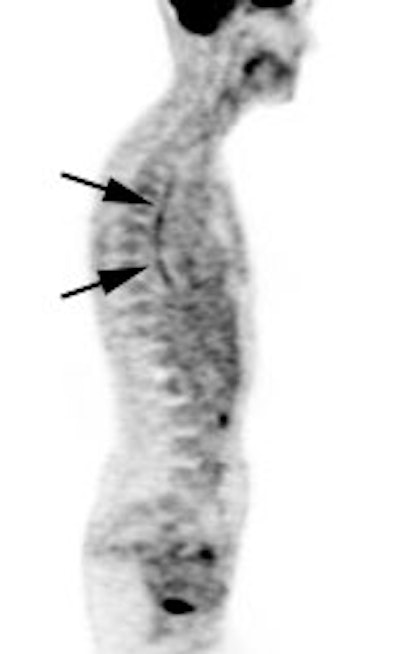

|

Marrow activity: The images below are from two separate patients each showing mild FDG accumulation within the vertebral bodies. |